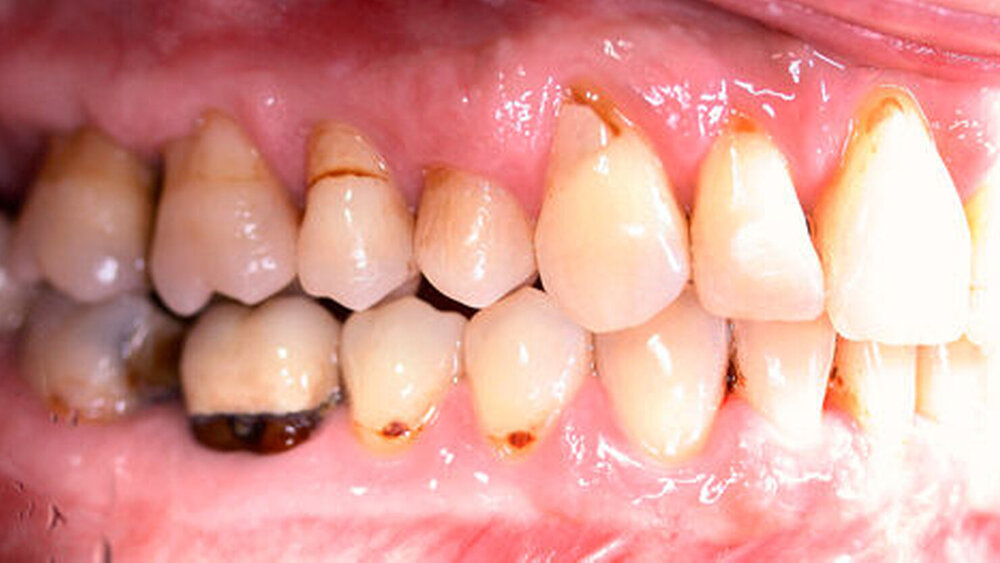

Anamnestisch lagen keine Besonderheiten vor. Es ist jedoch zu vermerken, dass ein regelmäßiger Alkohol-, Koffein- und Nikotinkonsum zugrunde lag. Intraoral zeigte sich ein bereits konservierend versorgtes permanentes Gebiss mit aktivem und inaktivem kariösen Geschehen. Große Anteile der Zahnhälse lagen nach Zahnfleischrückgang in Kombination mit Knocheneinbrüchen frei. Zahn 27 wurde bereits extrahiert.

Eine Beurteilung der parodontalen Situation an Zahn 11 offenbarte mesial und distal Sondierungstiefen von jeweils 6 mm.

Kieferorthopädisch imponierte beidseits eine neutrale Verzahnung bei einem tiefen Biss von 5 mm – bedingt durch die Verlängerung beider Frontzahngruppen. Besonders Zahn 11 zeigte eine erhebliche Verlängerung und Protrusion mit einer sagittalen Frontzahnstufe von 5 mm. Sowohl die Frontzähne im Ober- als auch im Unterkiefer wiesen eine lückige Beziehung zueinander auf (Abbildung 1).